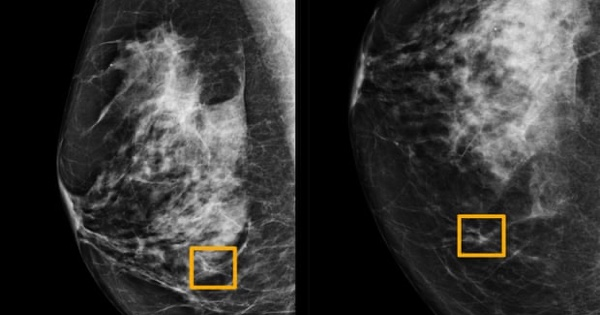

CHICAGO (Reuters) - A Google artificial intelligence system proved as good as expert radiologists at detecting which women had breast cancer based on screening mammograms and showed promise at reducing errors, researchers in the United States and Britain reported.

The team, which included researchers at Imperial College London and Britain’s National Health Service, trained the system to identify breast cancers on tens of thousands of mammograms.

They then compared the system’s performance with the actual results from a set of 25,856 mammograms in the United Kingdom and 3,097 from the United States.

The study showed the AI system could identify cancers with a similar degree of accuracy to expert radiologists, while reducing the number of false positive results by 5.7% in the U.S.-based group and by 1.2% in the British-based group.

It also cut the number of false negatives, where tests are wrongly classified as normal, by 9.4% in the U.S. group, and by 2.7% in the British group.